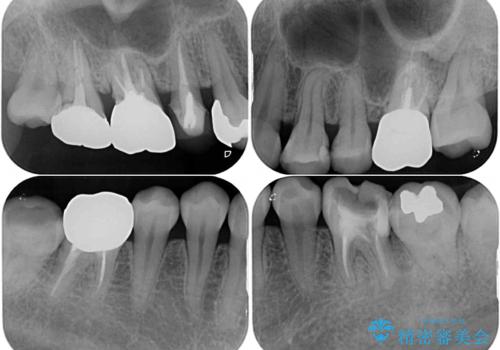

- 捻れた前歯と目立つ銀歯を気にして来院された患者様です。

左下大臼歯は根管治療が必要であったため、矯正治療前に根管治療を行い、その後矯正治療を行うこととしました。

矯正治療後には期にある銀歯を全てセラミッククラウンなどで補綴治療することとしました。